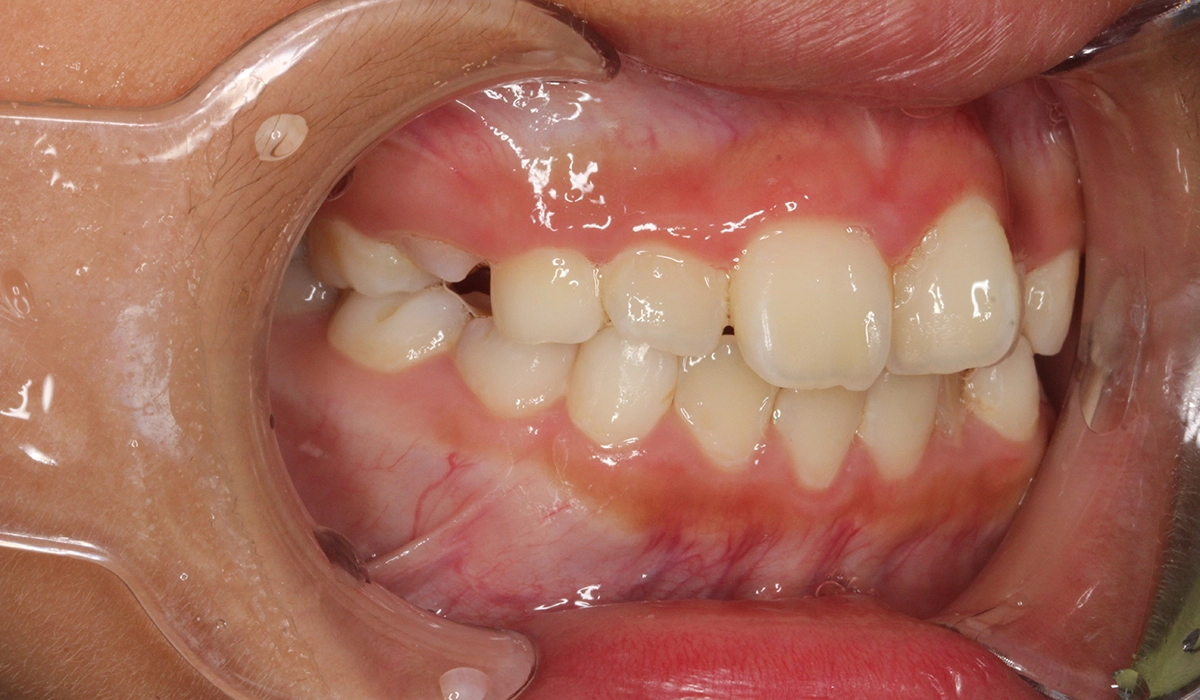

術前:右側